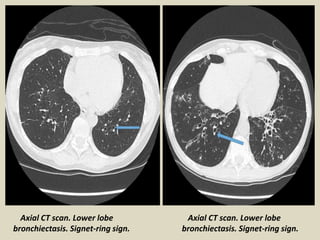

Axial CT scan. Lower lobe

bronchiectasis. Signet-ring sign.